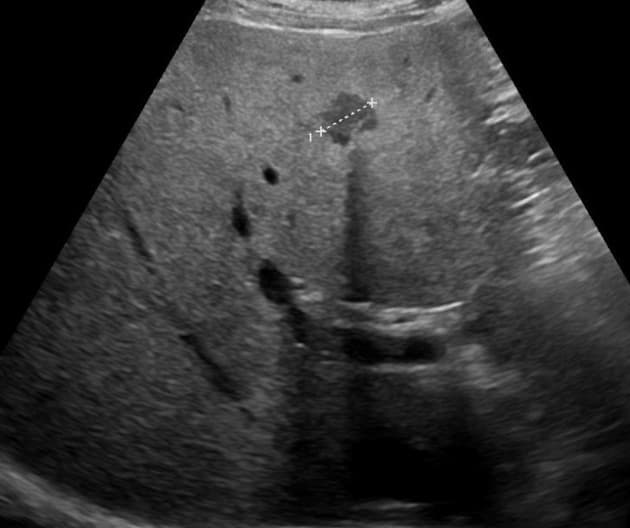

Siêu âm từ cơ sở y tế ngoài bệnh viện phát hiện một khối ở gan. Cần đánh giá thêm để xác định đặc điểm khối này.

- Trên hình ảnh T2, khối này tăng tín hiệu vừa phải (moderately hyperintense).

- Tuy nhiên, có một vùng lớn ở trung tâm khối, giới hạn không đều, giảm tín hiệu trên T2 và tăng tín hiệu trên T1, hình ảnh này gợi ý xuất huyết nội (internal hemorrhage).